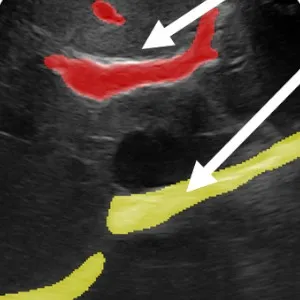

A deep learning approach for 2D ultrasound and 3D CT/MR image registration in liver tumor ablation Journal Article

In: Computer Methods and Programs in Biomedicine, vol. 206, pp. 106117, 2021, ISSN: 0169-2607.

abstract = {Background and Objective

Liver tumor ablation is often guided by ultrasound (US). Due to poor image quality, intraoperative US is fused with preoperative computed tomography or magnetic tomography (CT/MR) images to provide visual guidance. As of today, the underlying 2D US to 3D CT/MR registration problem remains a very challenging task.

Methods

We propose a novel pipeline to address this registration problem. Contrary to previous work, we do not formulate the problem as a regression task, which - for the given registration problem - achieves a low performance regarding accuracy and robustness due to the limited US soft-tissue contrast and the inter-patient variability on liver vessels. Instead, we first estimate the US probe angle roughly by using a classification network. Given this coarse initialization, we then improve the registration by formulation of the problem as a segmentation task, estimating the US plane in the 3D CT/MR through segmentation.

Results

We benchmark our approach on 1035 clinical images from 52 patients, yielding average registration errors of 11.6° and 4.7 mm, which outperforms the state of the art SVR method[1].

Conclusion

Our results show the efficiency of the proposed registration pipeline, which has potential to improve the robustness and accuracy of intraoperative patient registration.},